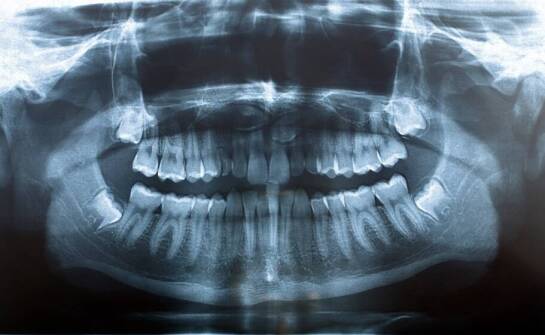

Rola zaawansowanej diagnostyki w leczeniu szczękowo-twarzowych wad

Diagnostyka odgrywa istotną rolę w ortodoncji, zwłaszcza przy wadach szczękowo-twarzowych. Technologie, takie jak skanowanie 3D, umożliwiają ocenę stanu pacjenta oraz planowanie leczenia. Dzięki temu lekarze mogą dostosować metody terapeutyczne do indywidualnych potrzeb, co może mieć znaczenie dla p